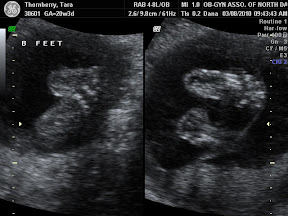

Today was the 'big scan'. It was so amazing. Seeing not only the girl's hearts beat, but seeing the four chambers of each of their hearts beating beautifully. The technician measured around their little noggins and their tummies. She measured the length of their legs and arms. We got to see their adorable little feet as well as their kidneys and stomachs. The technician even surprised us with a 4d picture of each of them. They're just beautiful. They've apparently already started sucking on their thumbs and playing footsie with one another. Baby A was especially active starting out head down, kicking her sister in the head, and then flipping over so that they were both feet down.

Baby A had a heart beat of 148 and was 14 oz and baby B had a heart beat of 152 and was 13 oz. Needless to say they are two very healthy girls.

Here are some of the pictures from today's visit:

Baby A stretchy legs:

Baby B feet: